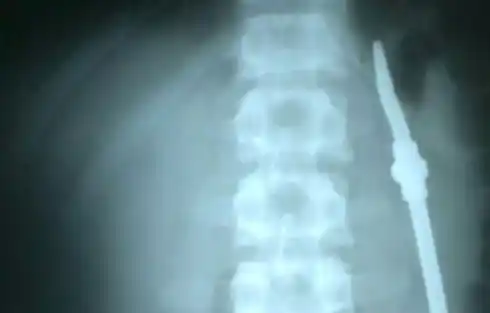

Entre Ríos: Operaron al preso que ingirió una bombilla

Evoluciona favorablemente el interno de la unidad penal N° 1 de Paraná que fue intervenido quirúrgicamente este jueves, luego de ingerir una bombilla. El hecho inusual se registró en la mañana de este jueves en la Unidad Penal N° 1 de Paraná: un interno se tragó una bombilla usada para tomar mate, a la que partió en dos. La ingirió frente a varios de sus compañeros. A raíz de la situación, el reo fue trasladado rápidamente al hospital San Martín, en donde se lo intervino quirúrgicamente.Así lo indicó el director del hospital San Martín, Eduardo Elías. "En una intervención quirúrgica, se pudo extraer el cuerpo extraño que ya se encontraba a nivel del estómago", dijo.Mencionó que si bien es muy pronto para establecer como evolucionará "debería hacerlo bien, aunque aún estamos en el post quirúrgico inmediato"."Ya pasó a sala", dijo también el director del nosocomio.A su vez el director del nosocomio mencionó que "es la primera vez que veo algo así, los cirujanos, por su función, sí han podido ver otros casos".Además puso relevancia en que "en la imagen radiológica se observa bien que en ese momento el objeto se encontraba a nivel esofágico. Cuando llega a quirófano estaba ya a nivel del estómago". (fuente: Elonce.com)